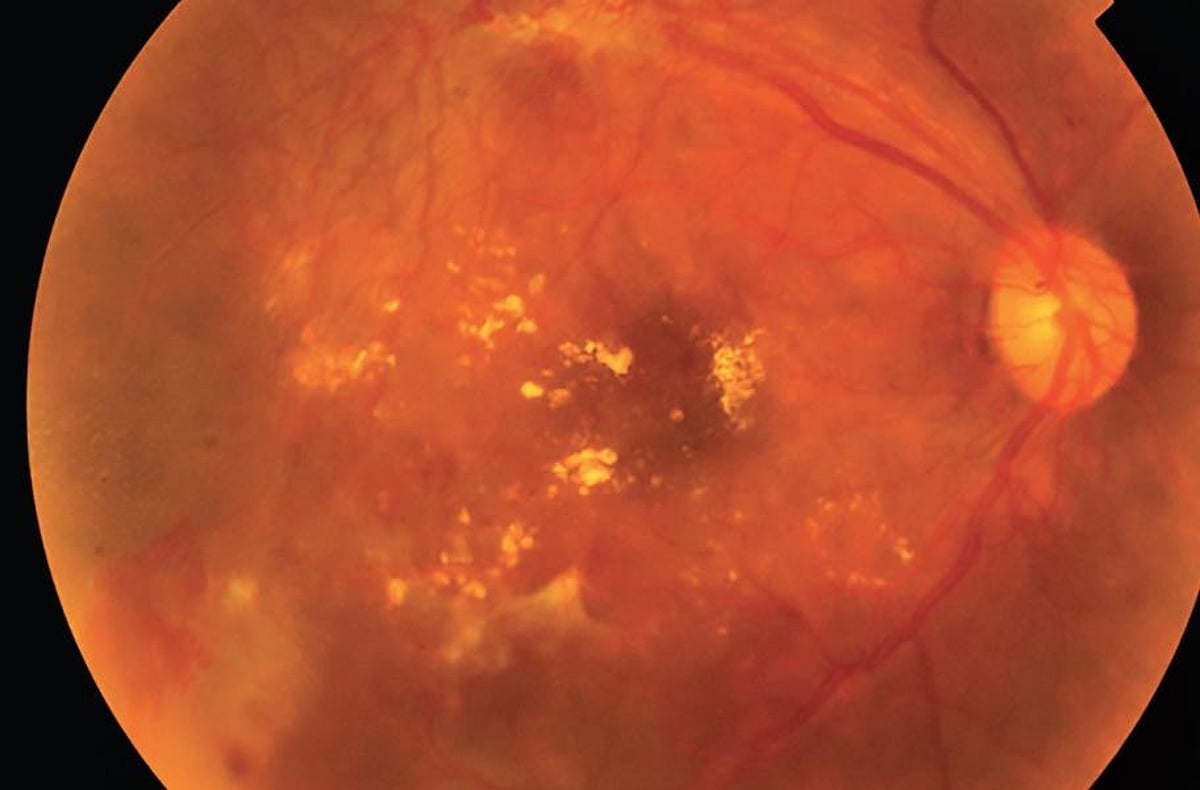

How technology is making the much needed retinopathy screening more accessible in India: Explained

He further emphasised the growing need for intervention in rural regions; “The rising incidence of d ...View More